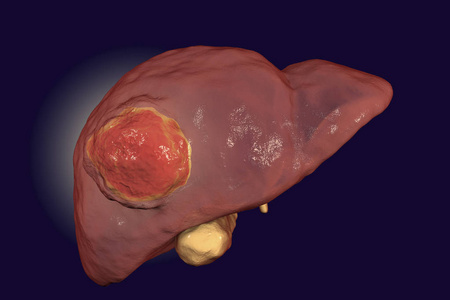

健康和肝癌肝脏矢量插图显微镜下的肝细胞肝细胞癌图肝细胞癌大鼠肝癌

肝细胞癌图肝脏的健康概念肝细胞癌大鼠肝癌, 60x 变焦手在蓝色手套与